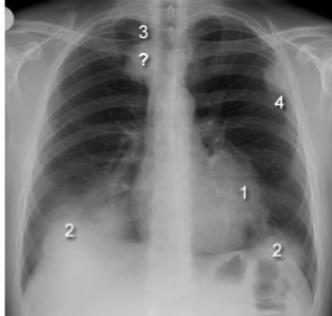

What are these silhouette signs? what causes them?

1: L Heart boarder (lingula disease), 2: Hemidiaphragm (lower lobe lung disease), 3: paratracheal stripe (paratracheal disease), 4: chest wall (lung, pleural or rib disease)